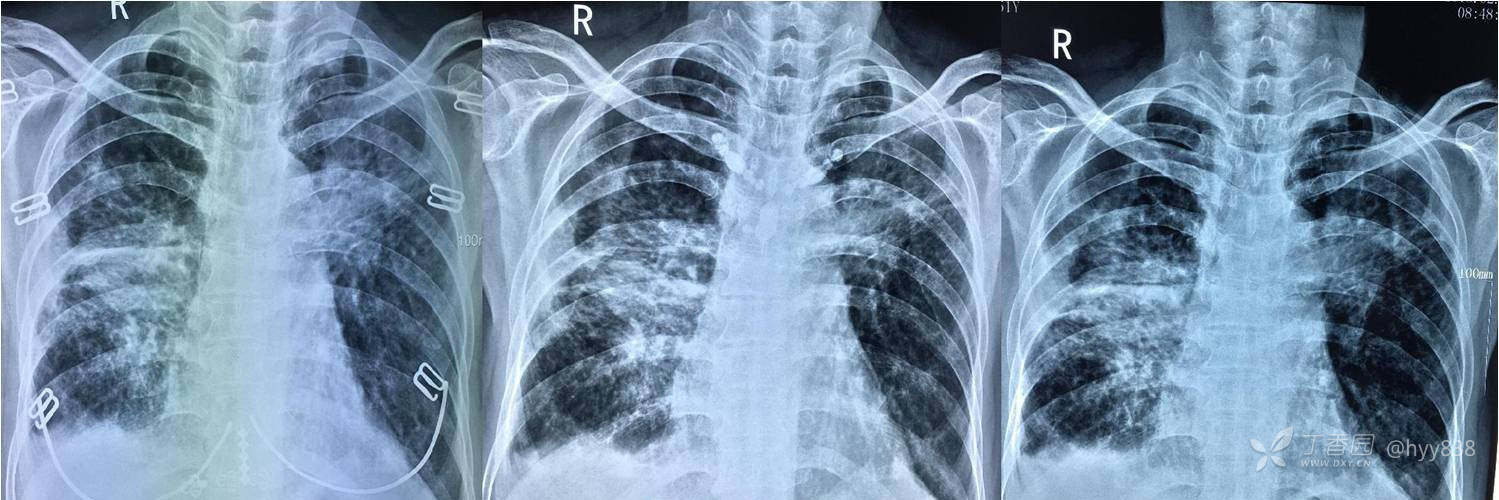

上半年抗痨治疗连续三个月复查

中间停药,下半年继续抗痨治疗

次年行CT复查,病灶进展